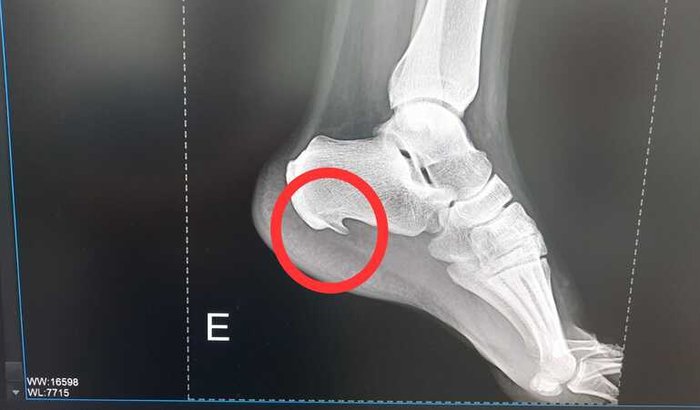

Fui diagnosticado com esporão calcâneo nos 2 pés, devido a isso sinto muitas dores ao ficar longos períodos em pé. Onde moro é complicado achar um trabalho onde facilite nesta situação. Venho por meio desta pedir a ajuda a vocês, pois somente com cirurgia conseguirei voltar a trabalhar e ter uma saúde melhor.